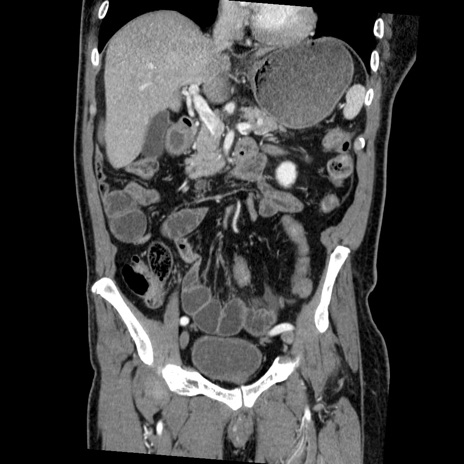

症例22(冠状断像)

【症例】50歳代男性

【主訴】腹痛

【現病歴】AVMからの被殻出血のため回復期リハ病棟入院中。 本日午後3時頃急に下腹部痛が出現した。

【既往歴】AVM、被殻出血、虫垂炎、高血圧

【身体所見】意識晴明、左半身不全麻痺、会話の理解は良好、36.5°C、腹部:膨隆、全体に板状硬、下腹部正中に圧痛点あり、反跳痛-、筋性防御不明、右下腹部にope scar

【データ】WBC 9400、CRP 0.06